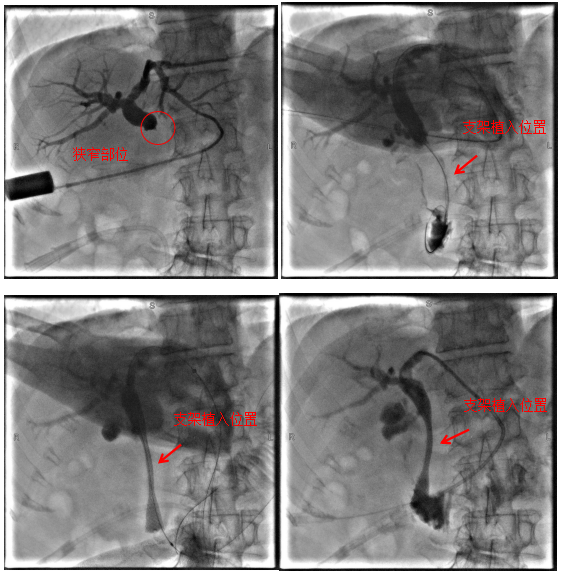

病例1

69歲老年患者,因“中上腹疼痛1周”于我院肝膽胰外科住院治療,完善相關(guān)檢查后考慮診斷為:胰腺惡性腫瘤、梗阻性黃疸等,因腫瘤分期晚并出現(xiàn)遠(yuǎn)處轉(zhuǎn)移,已無(wú)根治性手術(shù)指征,且因腫瘤侵犯十二指腸導(dǎo)致腸腔狹窄,無(wú)法實(shí)施ERCP+膽道支架植入術(shù)解除膽道梗阻,經(jīng)過(guò)科室團(tuán)隊(duì)充分評(píng)估,決定為患者行經(jīng)皮經(jīng)肝膽道支架植入術(shù),手術(shù)順利,術(shù)后患者黃疸逐漸消退,為后續(xù)治療提供了堅(jiān)實(shí)的保障。

術(shù)中影像